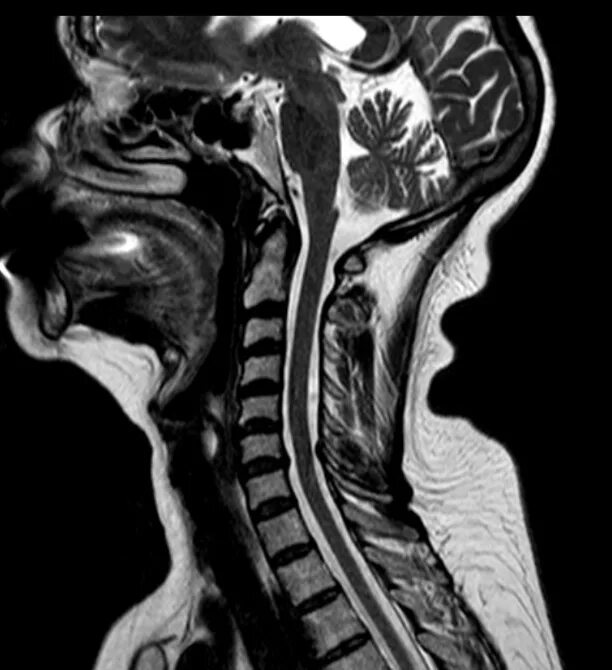

В шейном отделе мрт